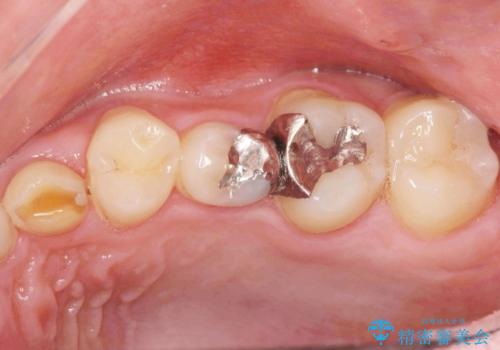

- ねじれてしまっている奥歯の矯正治療、銀歯のセラミック治療を求めて来院されました。

銀歯を外す前に部分矯正治療を行うことで歯のポジションを調整したのち、セラミック治療を行います。

90°ねじれてしまっていた歯を、矯正治療で治し、前後の歯の咬合関係も改善してしっかりと噛めるようになりました。